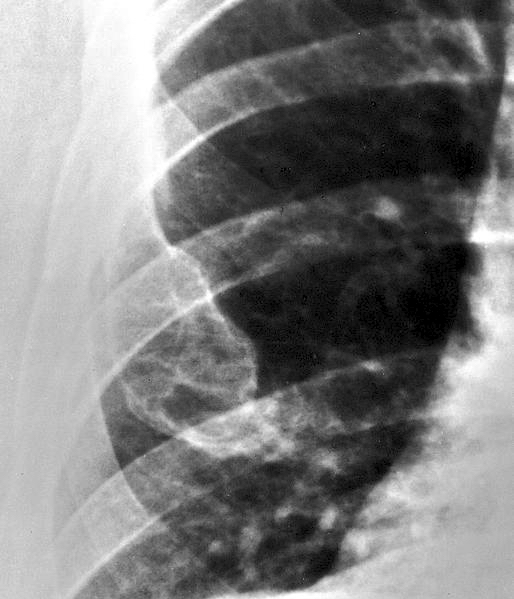

Radiology description

- Ill defined margins; diffusely radiopaque with ground glass image

- Single or multiple well circumscribed intramedullary lesions with a sclerotic rim

- May see cortical thinning as lesion expands

- Centered in metaphysis or diaphysis

- Radiolucent or ground glass appearance on Xray (Dorfman and Czerniak: Bone Tumors, 2nd Edition, 2015)

Radiology images